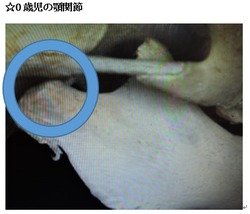

今回は、赤ちゃんの顎関節を考えていきたいと思います。

赤ちゃんの時は下の写真の様に顎関節がまだ存在しません。

赤ちゃんの時には顎関節は殆どない為に口を開ける事が苦手です。

今回は赤ちゃんの顎関節を考えていきたいと思います。

(上記の成人の蝶番部分が0歳時には存在しません。)